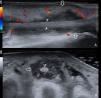

Una ecografía del pie determinó la presencia de efusión hipoecoica dentro de la vaina del extensor del tercer dedo a nivel del tercio medio y distal con moderada señal Doppler color y ningún incremento del grosor de la piel (fig. 1). Dado que habitualmente las ramas del extensor común de los dedos no tienen vaina más allá del tercio medio del antepié1, se confirmó el diagnóstico con una RMN (fig. 2). Iniciado el tratamiento antibiótico con vancomicina desde el primer momento, se realizó una limpieza quirúrgica al segundo día, drenándose 12cc de líquido de aspecto purulento en el que se identificó una cepa silvestre de Staphyloccocus aureus, que coincidió con los resultados de los hemocultivos.

La tenosinovitis infecciosa del pie se presenta con mayor frecuencia a nivel de los flexores plantares y se relaciona con la perforación tegumentaria por cuerpos extraños2, siendo muy rara su presentación en la región extensora del pie. Las tenosinovitis mecánicas de los tendones extensores se suelen relacionar con la exposición crónica a traumas repetidos3 como el que se produce en el síndrome del pie del ultramaratonista por contacto mecánico entre el tendón y una prominencia osteofítica proximal de las cuñas4. La celulitis del dorso del pie es el primer diagnóstico diferencial. El diagnóstico se puede realizar con una ecografía5 visualizándose el tendón inmerso en una vaina con contenido líquido hipoecoico y confirmándose con la aspiración y estudio microbiológico. La RMN permite, además, valorar la existencia de compromiso óseo6,7. El tratamiento antibiótico debe instaurarse ante la sospecha, aunque la duración y vía de administración es heterogénea en los escasos reportes de casos similares8–10. En nuestra opinión el compromiso sistémico justifica el manejo antibiótico intravenoso.